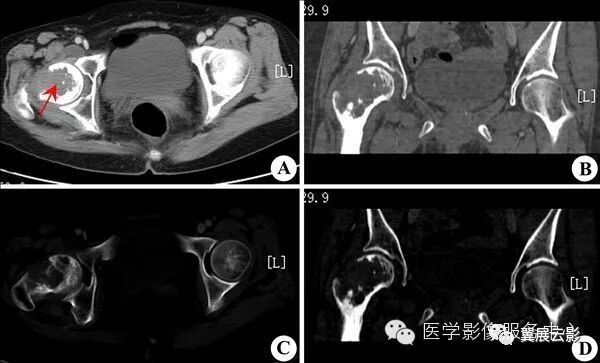

先天性和发育性髋内翻